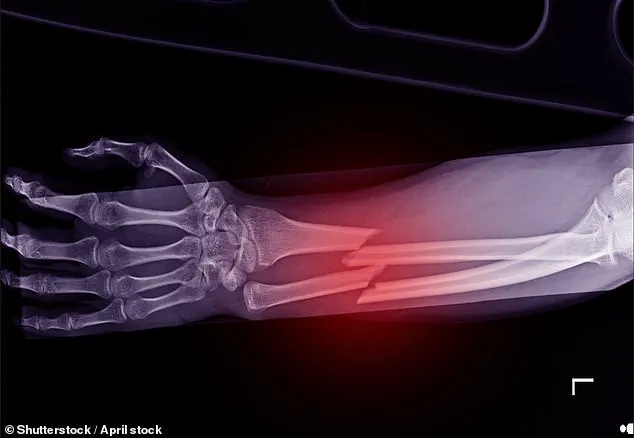

These services are critical for early diagnosis of osteoporosis, a condition that affects 3.5 million people in the UK and is responsible for one in two women over 50 suffering a bone fracture.

The National Institute for Health and Clinical Excellence (NICE) reports that more than a quarter of hip fracture patients die within a year, with one in ten dying within a month.

The Royal Osteoporosis Society estimates that 2,500 people die each year from preventable hip fractures, with its analysis projecting 74,000 preventable fractures by 2030—31,000 of which are life-threatening hip fractures.